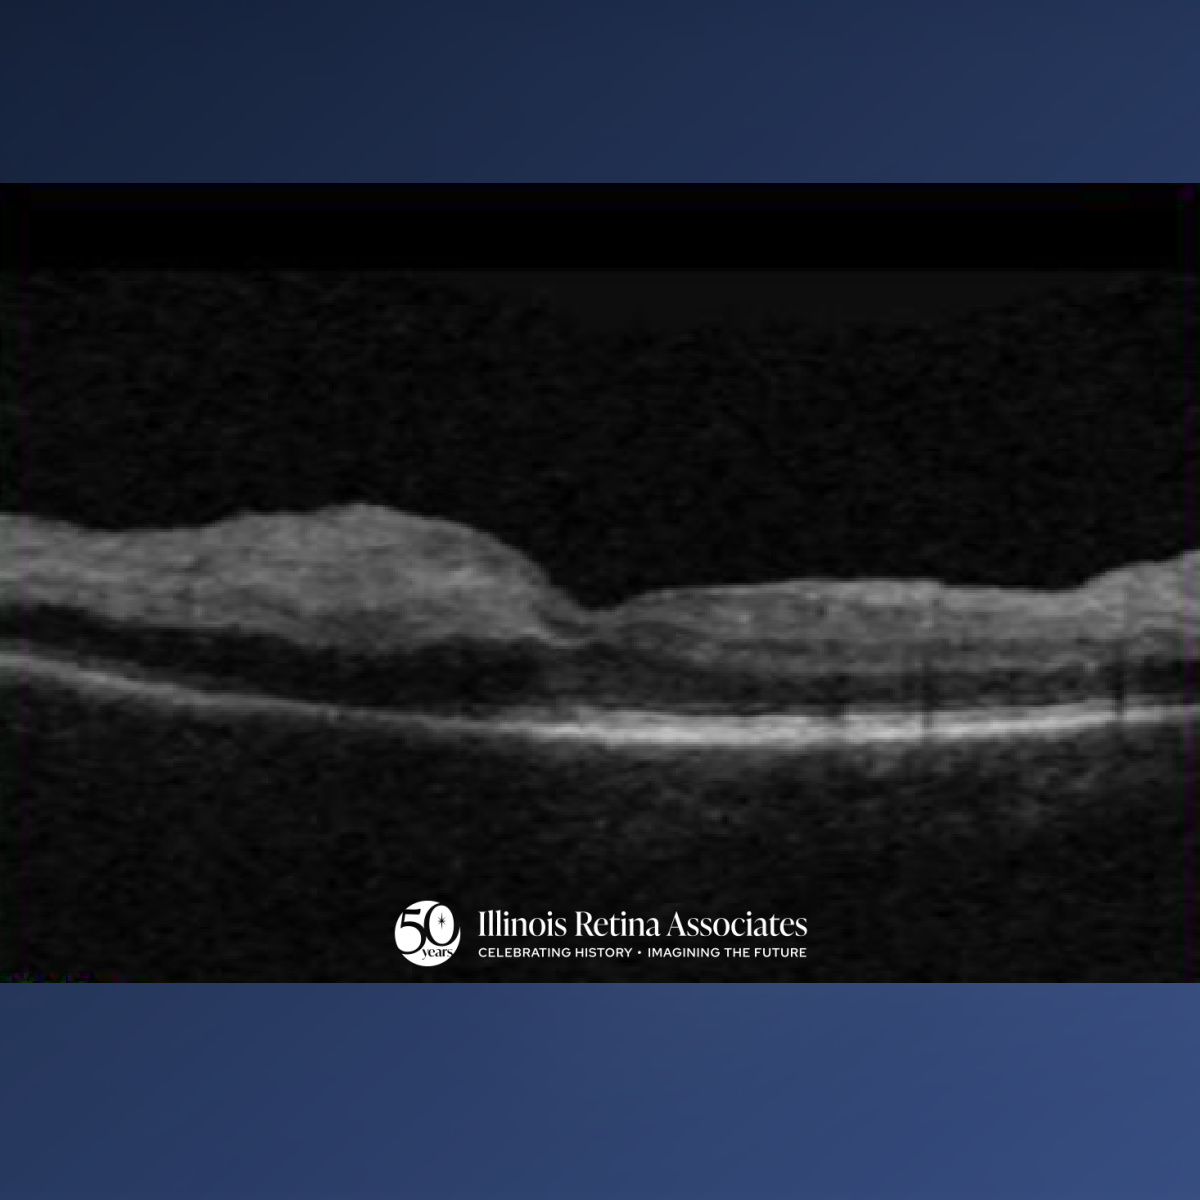

Visual acuity OD was 20/30 and OS was 20/25. Intraocular pressure was normal in both eyes (OU). Anterior segment was unremarkable apart from PCIOL OU. Posterior segment OD revealed 0.2 CDR, posterior vitreous detachment, arteriovenous nicking, mild epiretinal membrane, superior retinal whitening in the macula, prior retinal tear laser scarring but otherwise attached. Macula OCT OD showed superior inner retinal hyper-reflectivity and edema (Fig 1). Right eye fluorescein angiogram revealed significantly delayed AV transit time and extensive non-perfusion with area of sparing in the central macula in the late phase of 5 minutes (Fig 2).